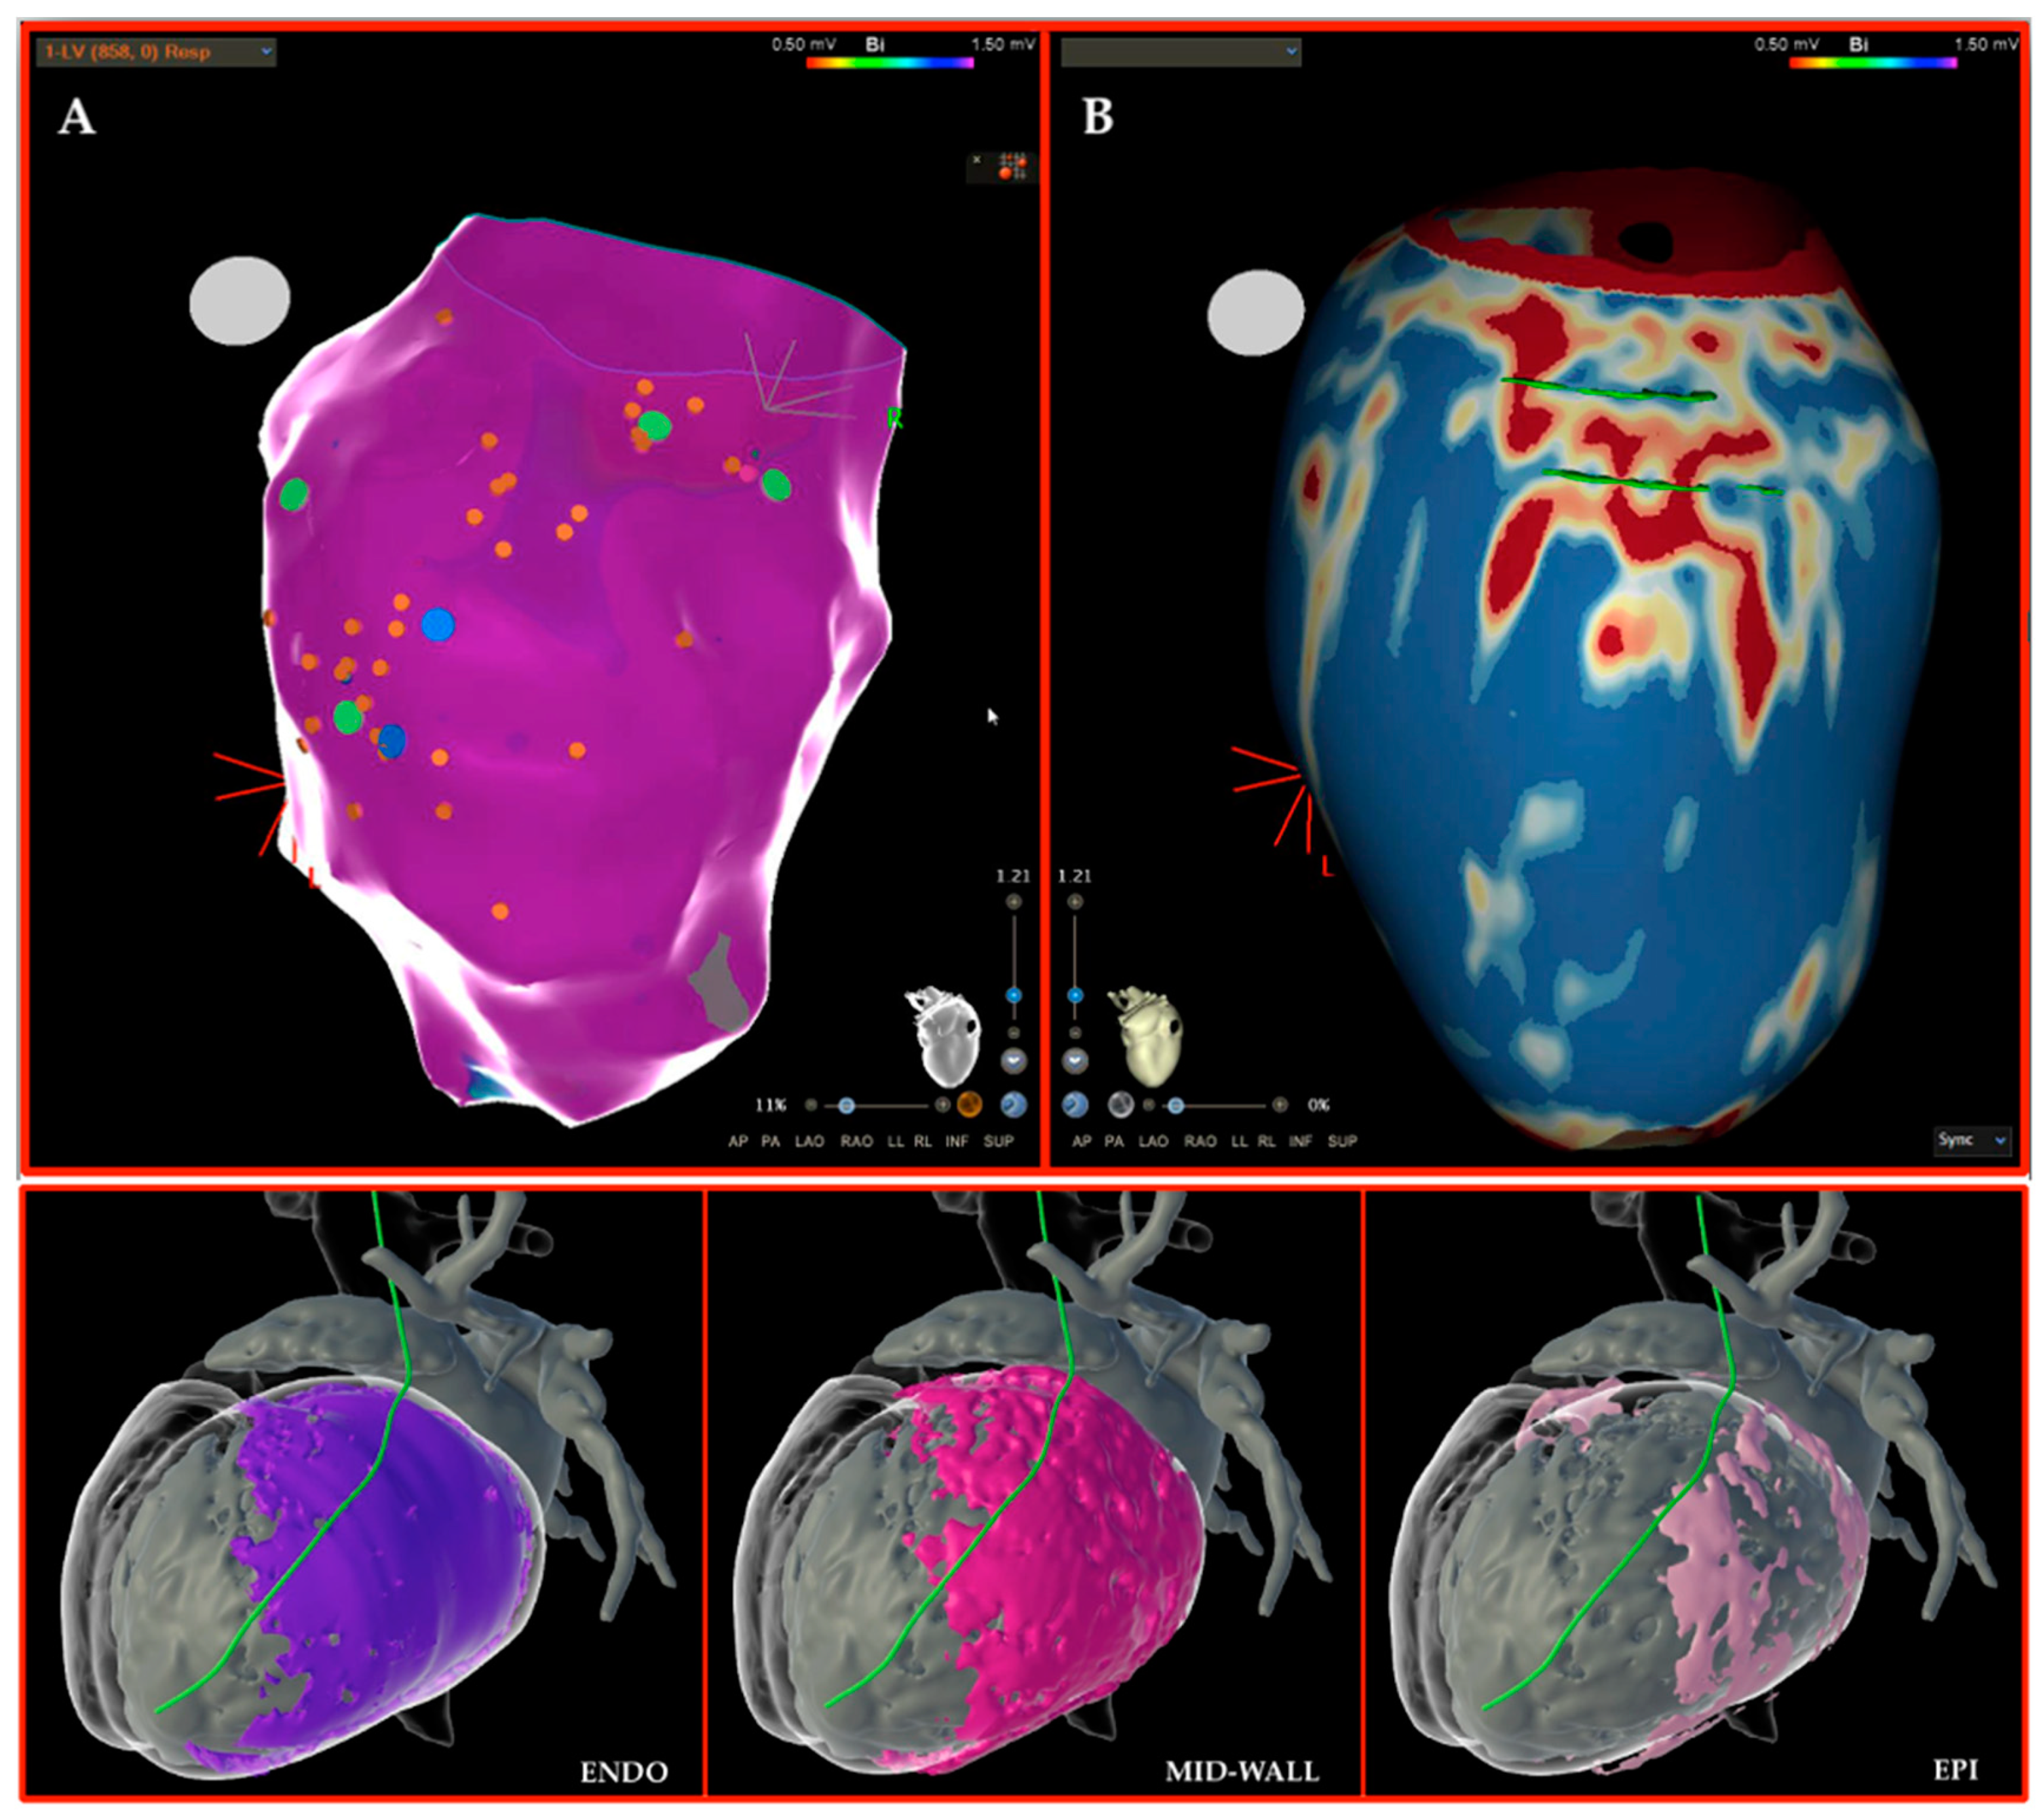

2.2. Cardiac Magnetic Resonance

2.4. Segmentation Software

4. Our Experience and Workflow